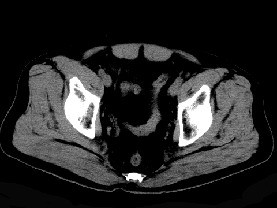

男,56岁,因左髋关节疼痛、无外伤史,体检左髋关节稍肿胀,请结合所提供图像,选择最佳选项()

A.左髋关节滑膜骨软骨瘤病

B.左髋关节退行性改变

C.左髋关节痛风

D.左髋关节滑膜炎

E.左髋关节类风湿关节炎

男,56岁,左髋关节疼痛、无外伤史,左髋关节稍肿胀,结合图像,最可能的诊断是()

[单选题]男,56岁,左髋关节疼痛、无外伤史,左髋关节稍肿胀,结合图像,最可能的诊断是()A . 左髋关节滑膜骨软骨瘤病B . 左髋关节退行性改变C . 左髋关节痛风D . 左髋关节滑膜炎E . 左髋关节类风湿关节炎

男,56岁,左髋关节疼痛、无外伤史,左髋关节稍肿胀,结合图像,最可能的诊断是()

[单选题]男,56岁,左髋关节疼痛、无外伤史,左髋关节稍肿胀,结合图像,最可能的诊断是()A .左髋关节滑膜骨软骨瘤病B .左髋关节退行性改变C .左髋关节痛风D .左髋关节滑膜炎E .左髋关节类风湿关节炎